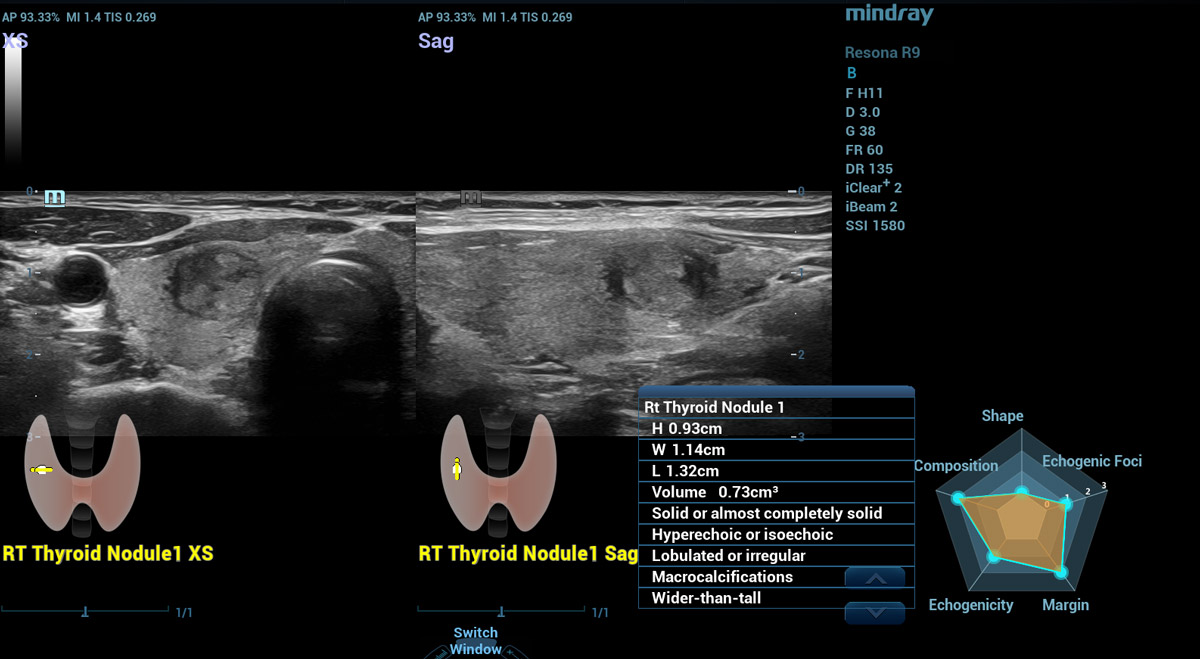

Smart Thyroid

Un altro piano, un'altra visuale

Smart Thyroid

Thyroid Ăš uno strumento di analisi e refertazione della tiroide che rende la routine clinica degli esami tiroidei piĂč accurata e produttiva.

Smart Thyroid nodulo